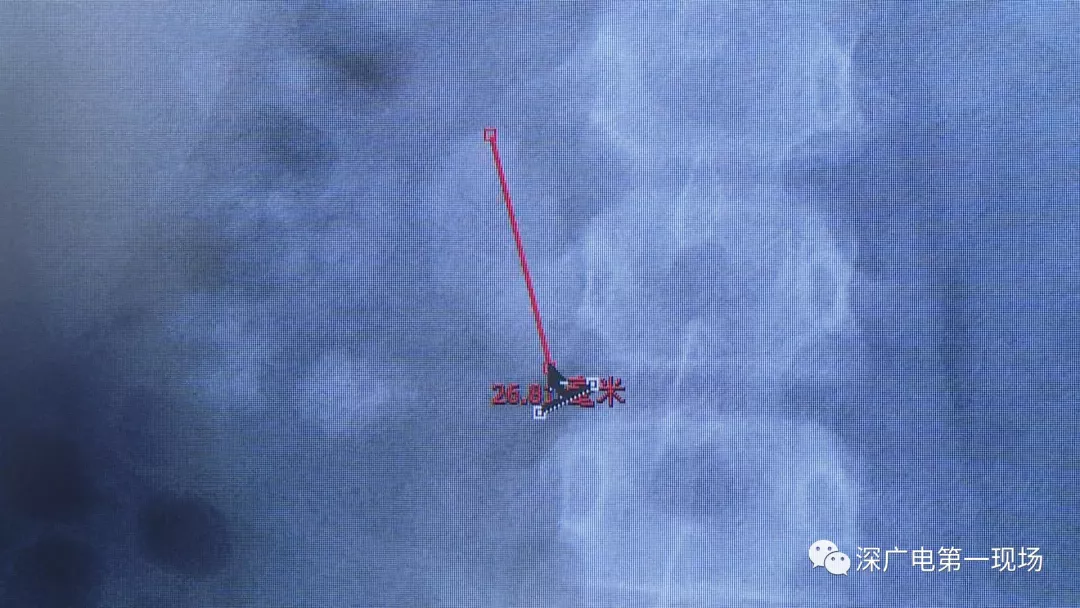

在X光圖像下,醫(yī)生發(fā)現(xiàn)小軒的雙側(cè)腎臟都內(nèi)藏乾坤,密密麻麻的分布著大小不等的結(jié)石。

醫(yī)生這么解釋:通常情況下,成人只要有0.5厘米大小的結(jié)石造成尿路梗阻,就需要及時(shí)治療。

小軒這種情況,其中,最大的結(jié)石長約2.7厘米,寬約1.7厘米,體積堪比鵪鶉蛋,不但造成了尿路堵塞,還導(dǎo)致了右腎中度積水。